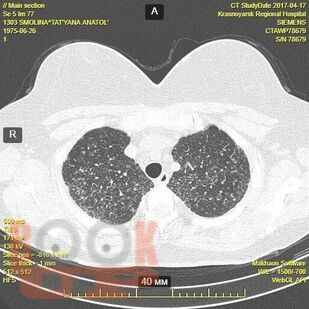

Гранулематозные заболевания легких

Гранулематозные заболевания легких : учебное пособие / И. В. Демко, Н. В. Гордеева, М. Г. Мамаева и др. - Красноярск : КрасГМУ, 2022. - 167 c. - Текст : электронный // ЭБС "Букап" : [сайт]. - URL : https://www.books-up.ru/ru/book/granulematoznye-zabolevaniya-legkih-19634258/ (дата обращения: 17.04.2026). - Режим доступа : по подписке.

Учебное пособие предназначено для врачей общей практики, участковых терапевтов, аллергологов, пульмонологов. В настоящем учебном пособии освещены принципы ведения пациентов с диссеминированными заболеваниями легких. Обсуждаются вопросы этиологии, патогенеза, диагностики, а также основные методы лечения.